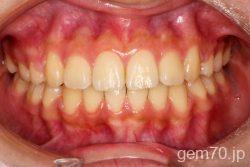

症状:開咬装置:セラミックブラケット | 抜歯世代:10代 | 高校生

主訴)前歯がかみ合わない

診断)開咬

使用装置)マルチブラケット装置

治療方法)抜歯 4|4/4|4

治療期間) 2年4ヵ月 通院回数 27回